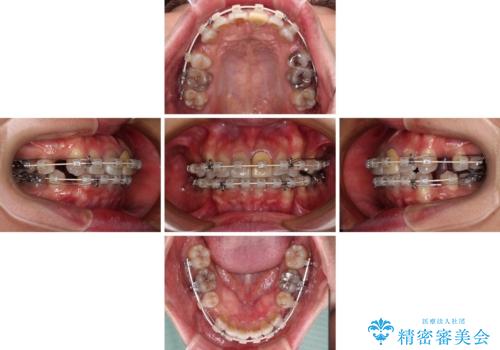

突出した前歯を引っ込める ワイヤー装置での抜歯矯正

- 矯正装置

- 審美装置

- 飛び出した前歯を気にして来院された患者様です。

口元を引っ込めるために上下左右の第一小臼歯4本を抜歯することとしました。

速やかに治療を進めたいとのことで、表側のワイヤー装置で矯正治療を行うこととしました。